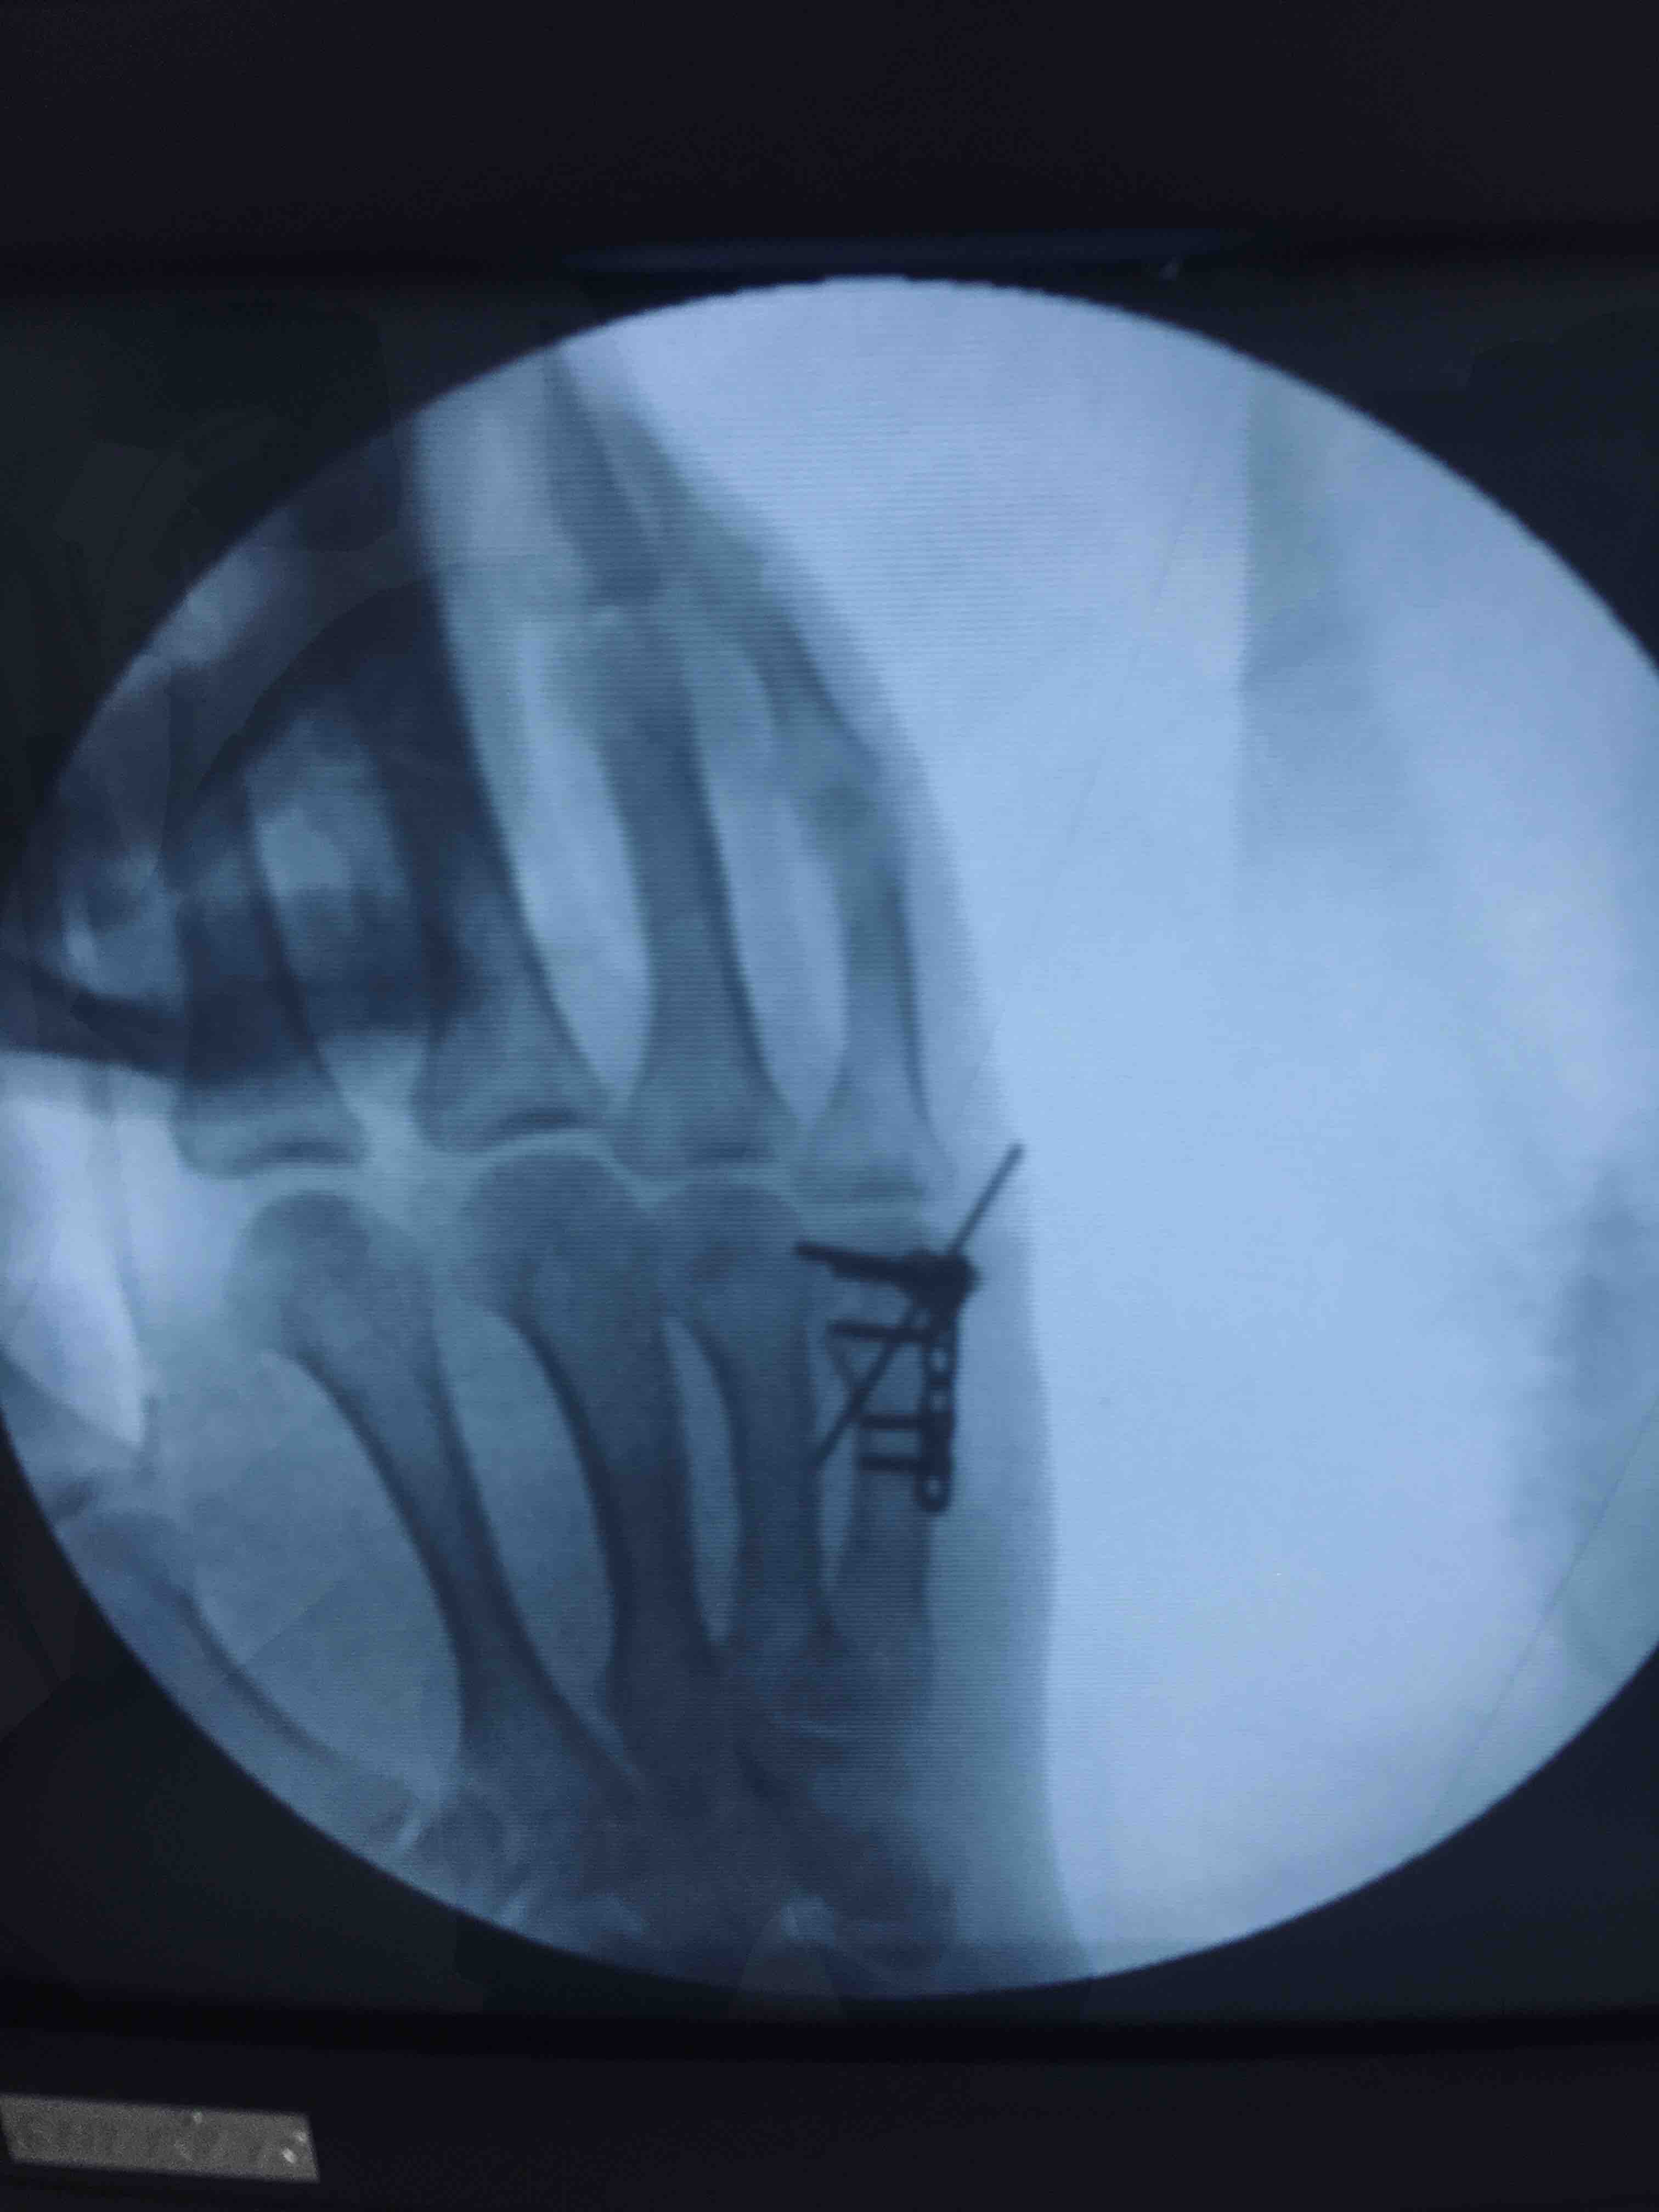

掌骨头粉碎性骨折(切复内固定术)

摔伤后右手疼痛1小时入院。既往因右手第五掌骨头骨折行闭合复位固定术。

右手第五掌指关节处肿胀,局部皮色皮温正常,压痛及纵向叩击痛阳性,末梢血运感觉正常,掌指关节活动受限。

臂丛麻醉下行切复内固定术,术后制动